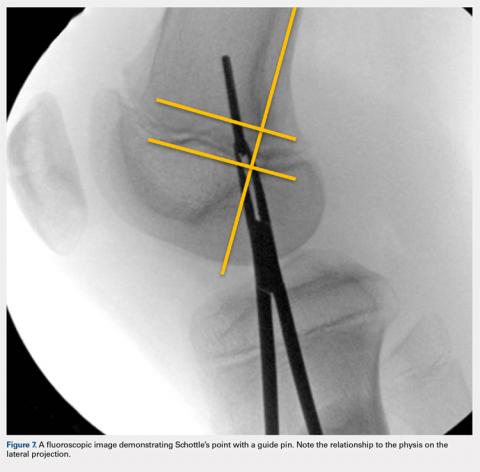

Fluoroscopy is now used to identify the origin of the MPFL on the medial femoral condyle. A perfect lateral is obtained by lining up the posterior condyle. Often, existent trochlear dysplasia will modify the normal appearance of the anterior structures of the condyles. Schottle’s point17 is USED to locate the origin of the MPFL. This is defined by drawing a line from the posterior cortex distally through the condyles (Figure 7). Two perpendicular lines are drawn, one to the extension of the posterior cortex at the level of the posterior extent of Blumensaat’s line and a second at the metaphyseal flare. Schottle’s point is located just anterior to the posterior cortex and in between these perpendicular lines. In a skeletally immature patient, this point appears to be at the level of the physis, on the lateral projection.